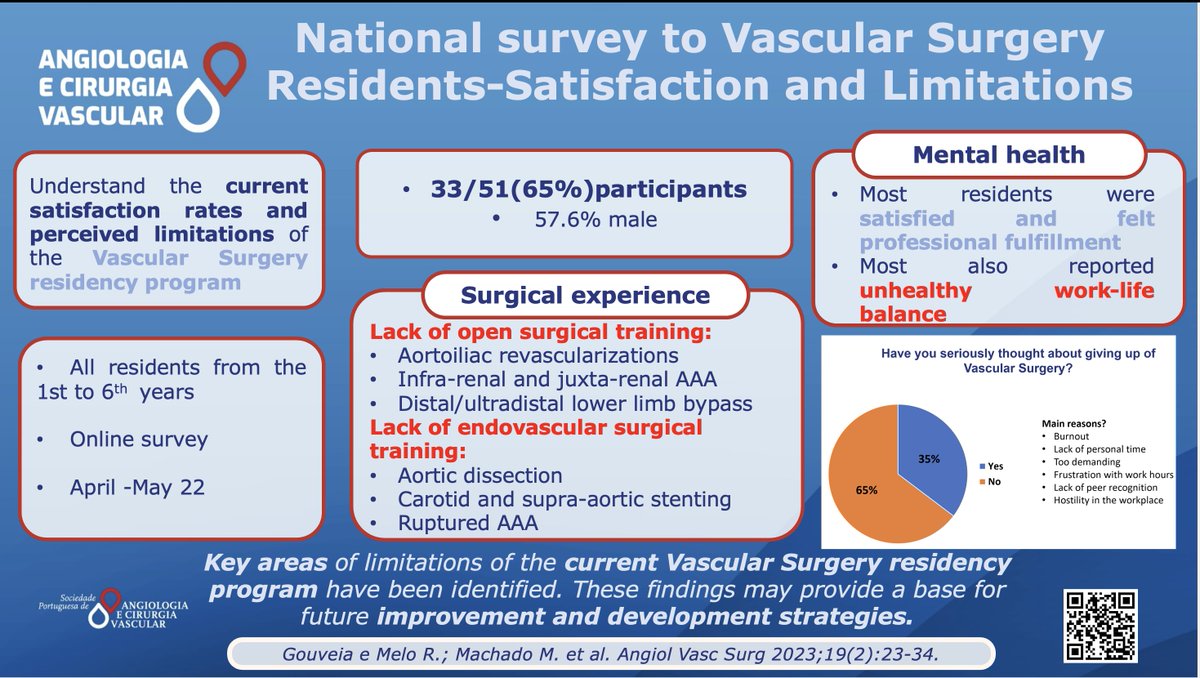

Have you seriously thought about giving up your residency program? 1/3 of Portuguese Vascular Residents answered YES Read more here: acvjournal.com/index.php/acv/… #vascularsurgery #residency #surgicalexperience #burnout #SPACV Ryan Gouveia e Melo Frederico Bastos Gonçalves